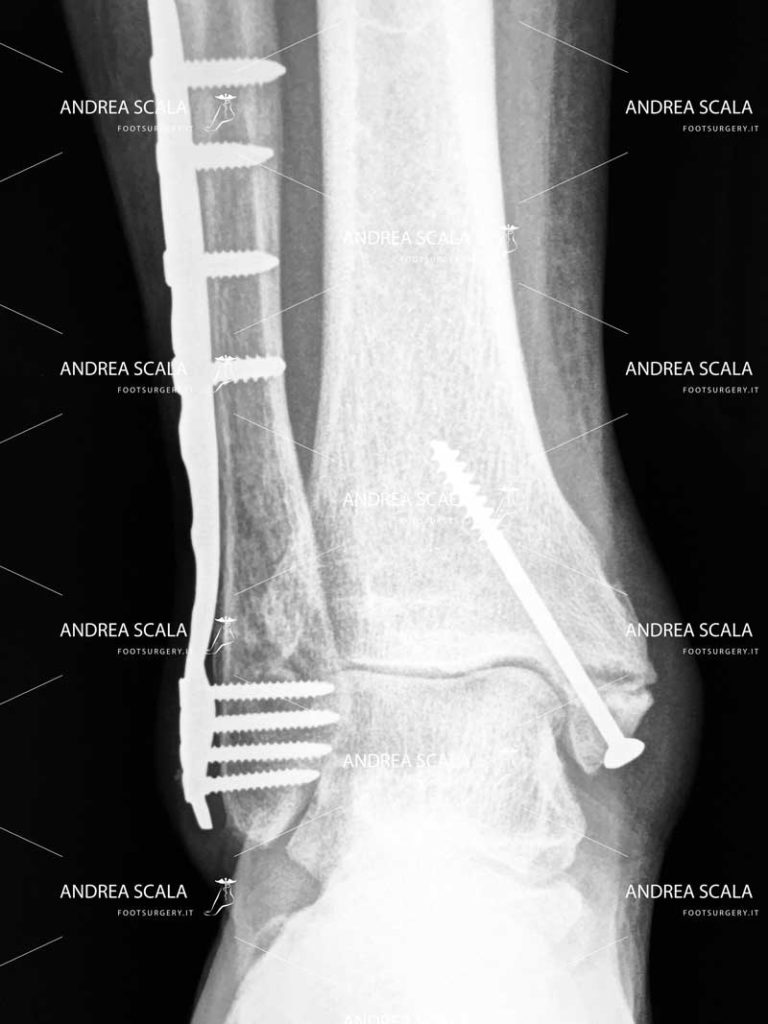

• Frattura di tibia e perone;

• Frattura malleolare (bi-malleolare o tri-malleolare);

• Frattura del pilone tibiale

L’Artrodesi della caviglia è l’intervento praticato dai medici 100 anni fa. Il blocco definitivo della caviglia toglie il dolore, ma comporta notevoli limitazioni funzionali. E’ un intervento molto invasivo e difficile. E’ difficile allineare le ossa della caviglia in buona posizione e le ossa non sempre consolidano.

La Protesi della caviglia è l’intervento che si esegue modernamente. L’intervento rimuove le parti consumate dall’artrosi. La tibia e l’astragalo vengono rivestite da componenti metalliche. Per separare le superfici metalliche viene inserito uno spaziatore in materiale sintetico (polietilene). Si ottiene un’articolazione artificiale ed è un’operazione analoga a quelle che viene effettuata sull’anca o sul ginocchio. Il grande vantaggio di questo intervento è la possibilità di mantenere il movimento dell’articolazione ma allo stesso tempo eliminare definitivamente il dolore. La durata dell’impianto si è allineata a quella della protesi d’anca e del ginocchio. I fattori importanti sono l’accuratezza dell’alineamento dell’impianto: la protesi deve replicare il funzionamento della caviglia normale. L’altro fattore importante per la durata della protesi è il mantenimento del meccanismo da parte del paziente: il paziente deve essere responsabile del corretto funzionamento dell’impianto protesico evitando stress e sollecitazioni anomale della caviglia, che consumano il meccanismo prima del previsto.